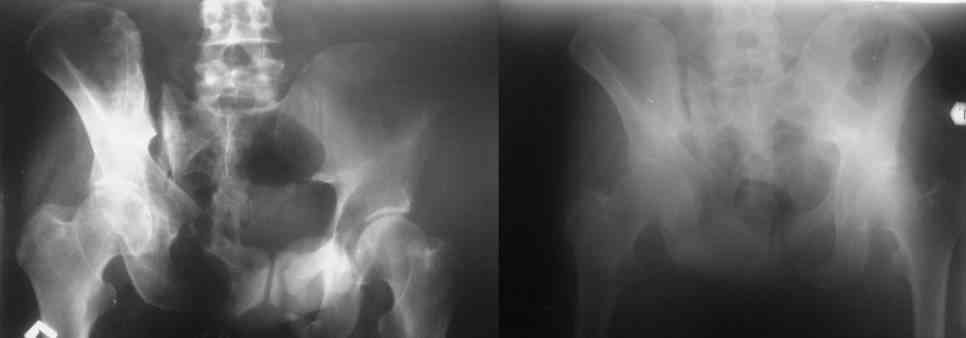

Остается только вариант закрытого аппаратного лечения. В аттаче положение отломков на вытяжении в прямой (АР) проекции. Для сравнения снимок до и во время вытяжения.

> Остается только вариант закрытого аппаратного лечения.. В аттаче

> положение отломков на вытяжении в прямой (АР) проекции. Для сравнения

> снимок до и во время вытяжения.

Первоочередно для тазовых операций важно обследование, снимки таза в инлет, оутлет и прямая

проекция.

На сравнительном снимке правый полутаз опустился

недостаточно, можно добавить вес и сделать все стандартные снимки.